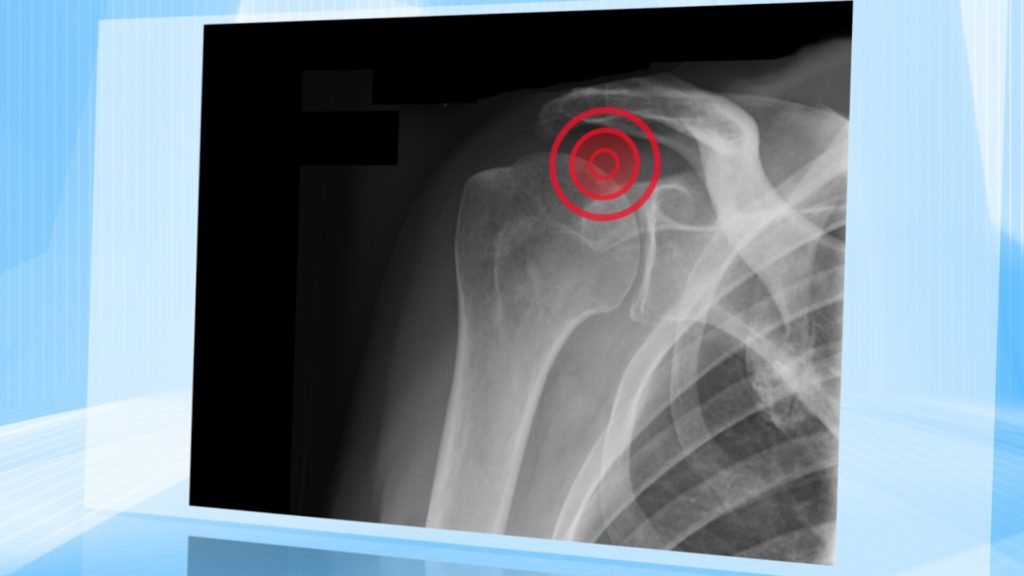

Sendungen 2018 Steife Schulter – ein hartnäckiges Problem Sendung vom 31. März 2018 Frozen Shoulder nennt sich eine häufige Krankheit der Schulter. Natürlich…admin31. März 2018